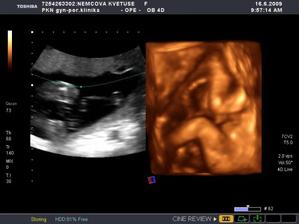

Nová naděje. Bohužel to bylo opět stejné, jako již dvakrát předtím. Třetí revize, třetí ztráta naděje. Jsem po laparoskopii a hysteroskopii a čekáme na výsledky imunologie v Plzni. Pak se uvidí co dál. V únoru 2009 nám v Sanusu doporučili ještě dva měsíce domácího snažení. Tak jsme se snažili a nyní napjatě sledujeme čárku. HCG nám krásně stoupá, 20. den po ovulaci je 2066. Máme 1. fotku dutinky. Přes nejrůznější potíže a patnáctidenní hospitalizaci nám miminko krásně roste. 22. dubna konečně po čtrnácti dnech ukázalo nosánek, máme nosní kůstku, NT je 2,0. Máme vše, co máme mít a rodiče se dnes poprvé společně dívali na ultrazvuk. Viděli mě i 4D, to koukali. Odnesli si video a teď na něj pořád koukají. Další kontrola náš čeká 5. května, opět ultrazvuk, triple testy a poradna. Trošku změna situace, mamka se mnou leží od 27. dubna v nemocnici, ale já ji dělám radost, rostu, 16.6. už vážím 360 gramů a od 5.6. ji kopu a ona o tom ví. Od 10. 6. se nám začal malinko měnit nález až jsme museli 10. 7., gr. h. 24+2 na cerclage, potom jsme měli zánět ledvin a astmatický záchvat. Pořád mamce tvrdlo břicho, tak se bez infuzí neobejde. 18. 7. se ještě objevilo krvácení, ale nebylo to nic závažného, byli jsme na ultrazvuku a vážím 908 gramů. V pátek 24.7. se to zlepšilo a kapeme na nejnižší rychlost, hurá. Mamka zatím nesmí chodit, má to slíbeno na 2. září. Kapeme sice na nejvyšší rychlosti, ale na ultrazvuku 4.8. mám odhad 1280 gramů. Dne 18.8. jsme byli na ultrazvuku a mám odhad 1750 gramů, mám trochu víc plodové vody a tak si tam plavu jako v bazénku. Dne 28.8. jsme byli s mamkou zase na ultrazvuku, vážím už 1950 gramů, mám udělaný krásný 3D fotečky, vody už nemám tolik moc, tak je mamka ráda. Jen se nám zase zkrátil čípek, už mě tam drží jen steh a 13 mm, ale držím mamce pěstičky, aby jsme vydrželi. No a taky si musím zvykat, mamka totiž má už dovoleno chodit na wc, a já jsem byl zvyklej, že pořád leží. Je sice z toho unavená, ale šťastná. Já jsem jí ještě udělal radost, že jsem se přetočil hlavičkou dolů. Dne 1.9. se mi konečně podařilo zbavit se té nitě, co tam mamka měla. Všichni jsou překvapení, jak se to mohlo stát, ale steh je pryč. Dne 10. 9. jsme s mamkou byli zase na ultrazvuku, vážím 2368 gramů (33+1). Hrdlo máme sice jen 9 mm, ale já se tam ještě udržím! Plodové vody mám už akorát, mamce klesly jaterní testy, žlučové kyseliny jsou v normě, tak má radost. Tak dnes 17. 9. jsem se byl zase vážit, mám 2517 gramů. Hrdlo má mamka jen 6,7 mm s obrovitým funnelingem, ale pořád drží. Denně mi točí monitory, mám je vzorné a pořád nemůžu přijít na to, jak ty sondy odkopnout. 26.9. pustil pan doktor mamku na propustku, byla poprvé 12 hodin mimo nemocnici, byli jsme na zahradě, grilovali jsme a já jsem babičce, dědečkovi a strejdovi předváděl, jak umím krásně kopat. Mamka byla moc šťastná. Večer se vrátila do nemocnice, dala si po 23. hodině sprchu a když usínala, tak jsem ji hodně překvapil, vypustil jsem svůj bazén. A tak se nešlo spinkat, ale na porodní sál. Šlo to pěkně a přesně ve 4.00 hodin jsem se narodil za skvělé asistence mého tatínka, který mamince na sále moc pomáhal. Vážím 2740 gramů a měřím 50 cm. Dosáhl jsem gestačního stáří 35+4. Rodiče a velká spousta lidí kolem ze mě mají velikánskou radost. Trošku jsem odmítal v inkubátoru dýchat, tak mě 1 den pomáhal CPAP. Večer mi ho vzali a teď už se snažím sám. mamka za mnou chodí a já jsem rád, když ji vídím. Dnes jsem na ni poprvé otevřel očička, snažím se papat, dnes už ze stříkačky. Tatínek je ze mě unešenej a já jsem rád, když mě přijde pohladit a vyfotit.